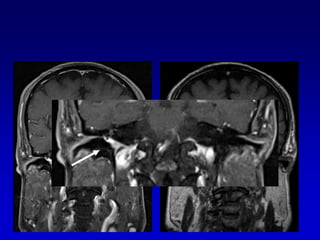

Lesión intracanalicular

AUMENTO DE VOLUMEN NODULAR EN EL CAIPlantea el diagnostico diferencial de Schwannoma conNeuronitisSchwannoma del nervio facial HemangiomaMeningiomasMetástasisLesiones menos frecuentes lipoma, quiste aracnoideo, linfoma, ependimoma y melanoma.

Lesión intracanalicularScreening con  T2 DRIVEExclusión con secuencias T1 Gd que son las secuencias mas sensibles para el Schwannoma intracanalicular, pero no siempre especificas, a veces es difícil la diferenciación con neuritis